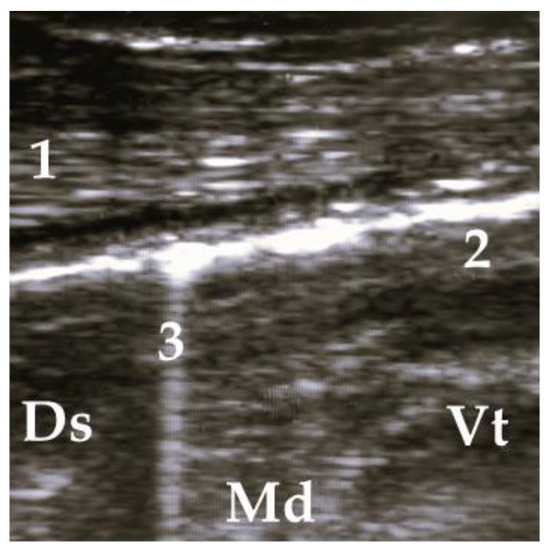

2.5. Ultrasonographic Examination

4.2. Assessment of Ultrasonographic Findings of Respiratory Disease

4.3. Association between Antemortem Physical and Ultrasonographic Examination Scorings and Scorings of Postmortem Inspection